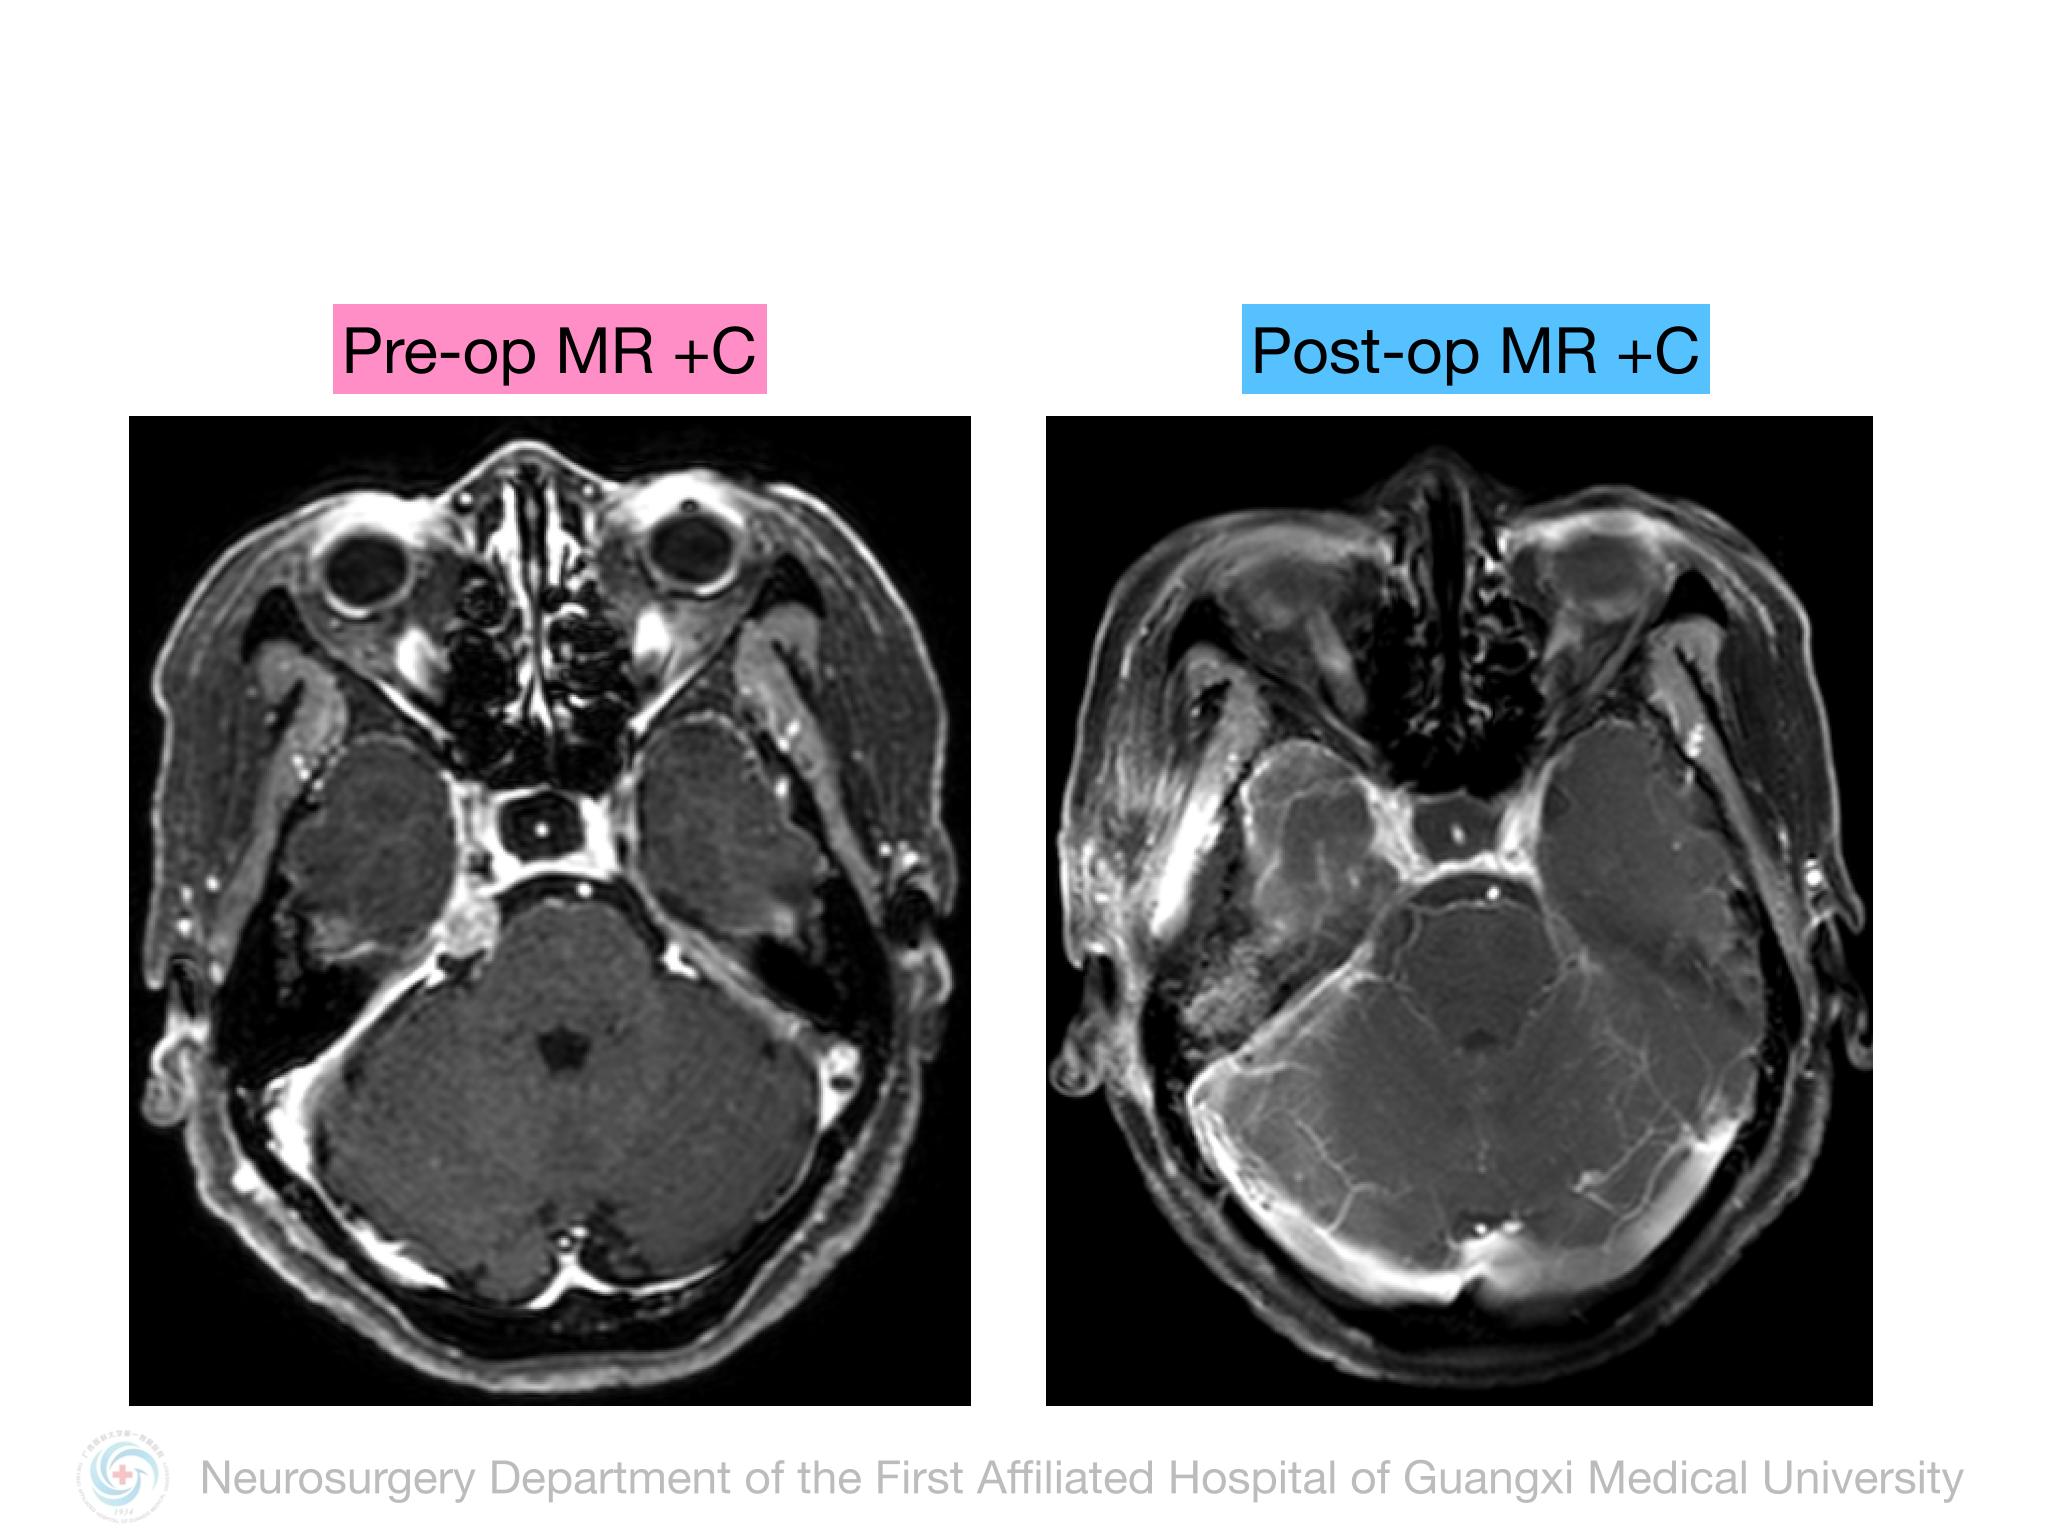

Meckel’s cave(MC)由多层硬膜围绕三叉神经半月结构成,通过三叉神经门与后颅窝蛛网膜下腔相通,起源于MC的脑膜瘤并不常见,文献报道约占所有颅内脑膜瘤的1%。Samii教授报道将MC脑膜瘤分4型,I型:局限于MC;II型:MC脑膜瘤向中颅窝扩展或海绵窦浸润;III型:MC脑膜瘤向CPA区扩展;IV型:MC脑膜瘤向中后颅窝均有扩展。本例属于I型,局限于MC,因此首选颞下经天幕入路,结扎岩上窦,显露部分岩尖,必要时硬膜下磨除岩尖。术中需注意颞叶及Labbe静脉壁保护,避免损伤岩静脉,尽可能全切肿瘤及基底。本例术中见肿瘤基底位于MC外侧壁及顶壁,主体位于MC,向后下推挤三叉神经,向后颅窝有部分延伸,但与脑干无黏连,向三叉神经内侧进入MC内侧空间,充分显露MC后将肿瘤及其基底全切,周围神经血管保护良好,术后无新发神经功能障碍,疗效满意。